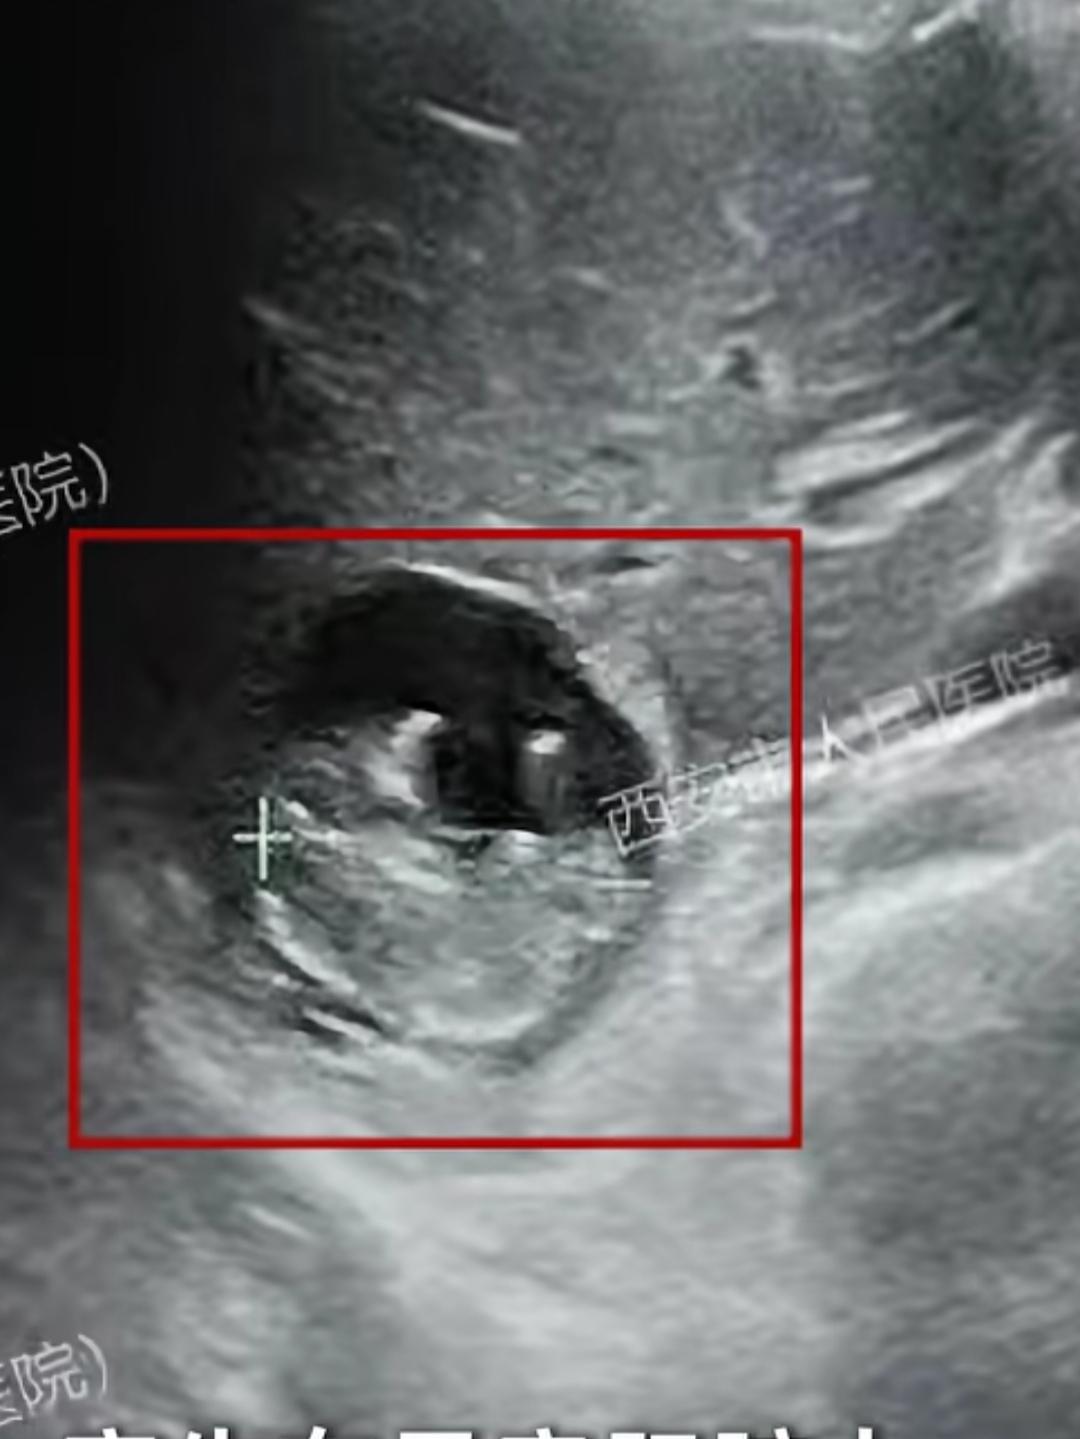

“心肝宝贝”就是这么来的! 近日,50岁的王女士抽血检查后发现自己怀孕了。 然而,医生用B超在子宫和输卵管附近检查,却始终找不到孕囊。 起初以为是抽血检查出错了,随后在西安市的医院检查后,竟发现胎儿寄生在她的肝脏上。 ‘肝脏妊娠’病死率是宫外孕的7倍、宫内妊娠的90倍。 全球此类病例不超过50例,后期会引发致命性大出血,必须紧急手术。 王女士切除了孕囊及附着的部分肝脏,目前恢复状况良好。 宫外孕己经少见了,这个‘肝脏妊娠′,着实比较稀奇!